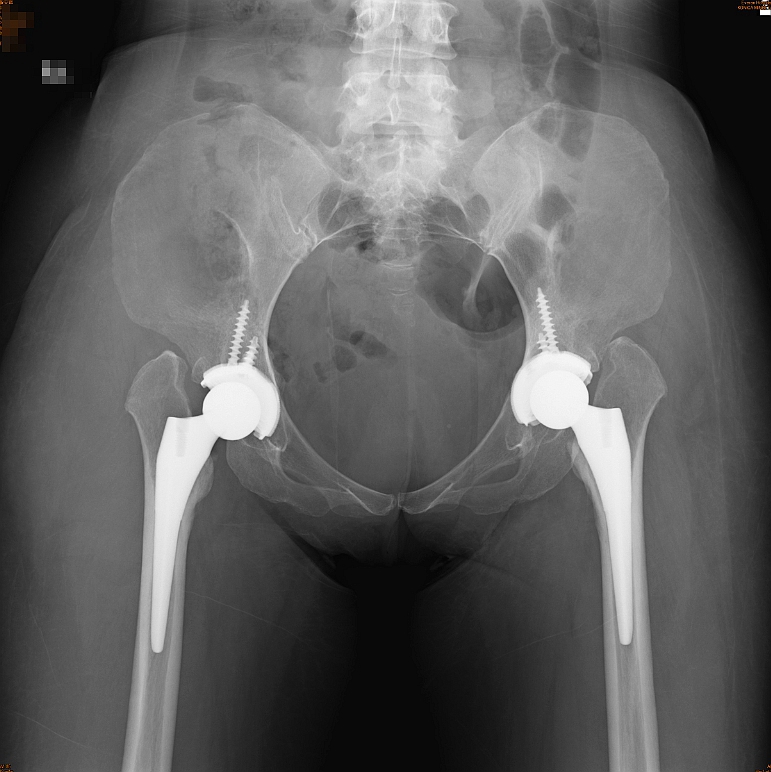

長安醫院骨科主任楊志鴻醫師表示,由黃小姐髖部的X光片明顯可見,她原本就有先天性髖關節發育不全的問題,因跌倒撞擊的關係,更導致右側髖關節往上位移近9cm,手術困難度相對較高,對患者而言要承受相當大的風險,故建議她透過「機器人手臂髖關節置換術」,在骨科醫療團隊合作下,完成精準定位置換雙側髖關節,從X光片的位置和角度,皆符合人體工學和解剖構造位置,術後二個月,患者即重回正常的生活型態,是一般髖關節手術所無法達成的雙髖置換新技術。